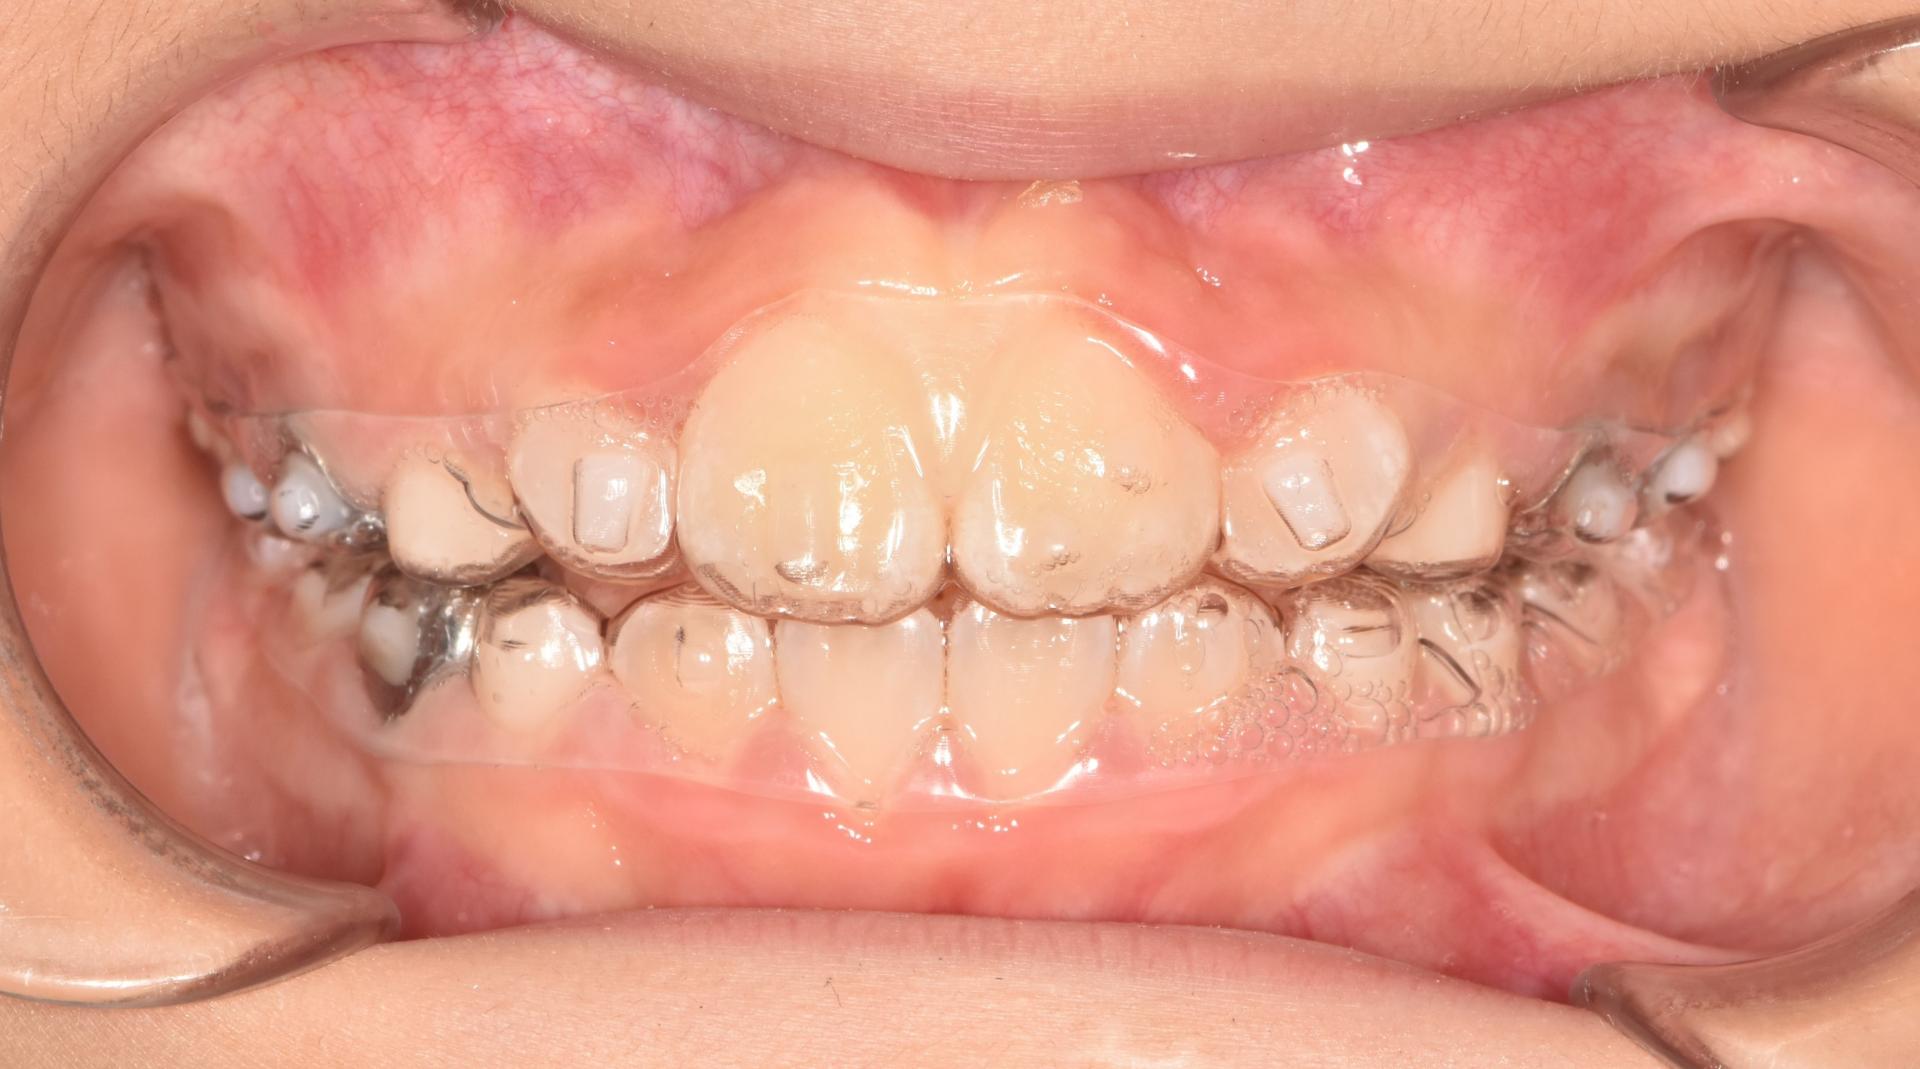

투명교정장치 착용중. 장치를 착용하여도 티가 나지 않습니다. 아이는 정말 성실하게 장치를 잘 껴주었습니다.